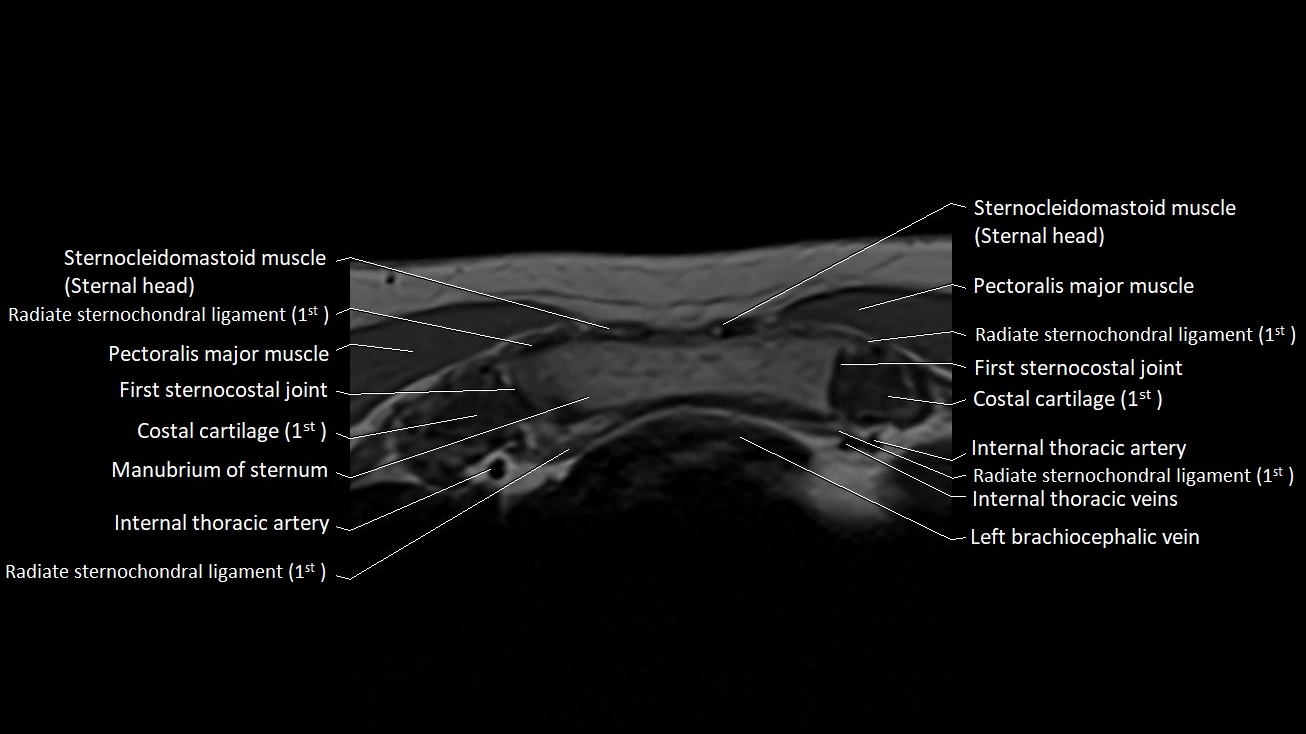

MRI images

image